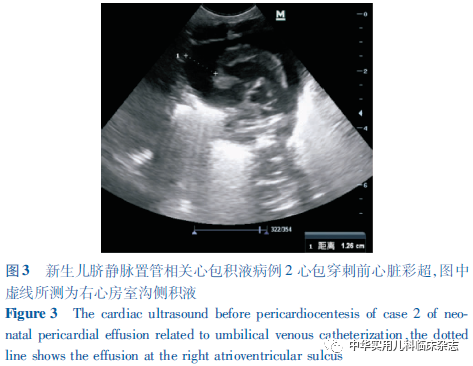

病例资料1.1 病例1 患儿,男,胎龄33+4周,第2胎,第3产,出生体重2 150 g,Apgar评分1 min 8分,5 min 9分,出生后因“早产、呼吸费力10 min”,以新生儿呼吸窘迫综合征(NRDS)收入武汉大学中南医院妇儿医院儿科NICU。入院后予经鼻持续气道正压通气(nCPAP),出生后10 h予UVC(法国美德 PRODIMED 3.5F),过程顺利,置管深度采用Shukla公式计算(1.5×出生体重+5.6+脐带残端长度)[2],床旁X线示导管尖端位于胸椎T8水平。出生后34 h患儿出现血氧饱和度(SpO2)、心率(HR)及血压(BP)下降,肤色苍灰、发花,呼吸节律慢,心音微弱,立即行气管插管及复苏囊正压通气,SpO2缓慢回升,但HR仍持续下降,予生理盐水扩容、肾上腺素强心、碳酸氢钠纠酸及持续心肺复苏,效果不佳。急行床旁彩超提示心包腔大量液性暗区(图1),立即行心包穿刺及闭式引流,术后患儿生命体征逐渐平稳,连续2 d复查彩超均未显示心包积液,复查胸片见UVC导管尖端上移至胸椎T6水平(图2),遂予拔除。心包积液送检结果提示:葡萄糖69.24 mmol/L,乳糜实验阴性,细菌培养阴性,与当天输注的不含脂肪乳静脉营养液成分相符,考虑心包积液主要为经UVC渗漏的静脉营养液。患儿住院治疗24 d出院,目前10月龄,生长发育良好,无心血管及神经系统后遗症。1.2 病例2 患儿,男,胎龄31周,第3胎,第2产,出生体重1 830 g,Apgar评分1 min 7分, 5 min 8分, 10 min 7分,经新生儿复苏后以NRDS收入院。入院后给予气管插管、肺表面活性物质(PS)气管内注入后行呼吸机辅助通气。出生后8 h顺利行UVC置入, 床旁X线定位导管尖端于胸椎T8水平。出生后第2天,患儿于呼吸机支持下仍可见呼吸窘迫表现,予第2剂PS气管内注入。同日夜间,患儿突发SpO2持续下降,肤色苍灰、发花,四肢冰冷,呼吸节律慢,心音低钝、遥远,立即心肺复苏并予扩容、纠酸、利尿及肾上腺素强心等处理,患儿心音仍低钝,肤色仍灰,且气管导管内可见鲜血涌出。急行床旁心脏彩超提示心包腔大量积液(图3),胸片提示UVC尖端移位至T5~T6,心影增大(图4A),立即拔除UVC并行心包穿刺引流术,抽出淡黄色乳糜样液体约20 mL,术后患儿生命体征渐平稳,肺出血停止。术后第1-3天多次复查心脏彩超均未见心包积液,复查胸片见心影较前缩小(图4B)。心包积液送检结果提示:葡萄糖88.66 mmol/L,乳糜实验阳性,细菌培养阴性,与当天输注的含脂肪乳静脉营养液成分相符。此后患儿由于支气管肺发育不良等早产儿常见疾病继续治疗,共住院47 d出院。患儿目前9月龄余,生长发育良好,无心血管及神经系统后遗症。1.3 病例3 患儿,男,胎龄27+6周,第2胎,第2产,因其母“重度先兆子痫;抗磷脂综合征高同型半胱氨酸血症、黑尔普综合征”剖宫产娩出,出生体重850 g,Apgar评分1 min 5分,5 min 6分,10 min 7分,经新生儿复苏后,携气管插管于T组合通气下转入院。入院后予PS气管内注入及高频呼吸机辅助通气。出生后2 h 行UVC置入,行床旁X线检查示导管尖端位于胸椎T9水平。出生后第1天复查胸片见UVC尖端移至T5水平(图5A),予外拔1.5 cm使之回至T9水平。出生后第5天,患儿于双相气道正压通气下,出现明显呼吸困难,遂再次行气管插管及呼吸机支持。同日夜间患儿突发全身发绀,气管导管内可见鲜血,SpO2、HR、BP无法测出,听诊双肺呼吸音低,心音极其微弱、遥远,立即行心肺复苏,予肾上腺素强心、碳酸氢钠纠酸、生理盐水扩容,患儿症状无改善。急诊床旁胸片见心影明显增大(图5B),彩超提示心包积液(图6)、右侧胸腔积液,立即行心包及胸腔穿刺,抽出乳糜样混浊液体共20 mL后复查彩超未见明显心包及胸腔积液。持续心肺复苏、液体复苏及间断电除颤,患儿自主呼吸及HR仍未恢复,抢救持续约3 h后宣告临床死亡。